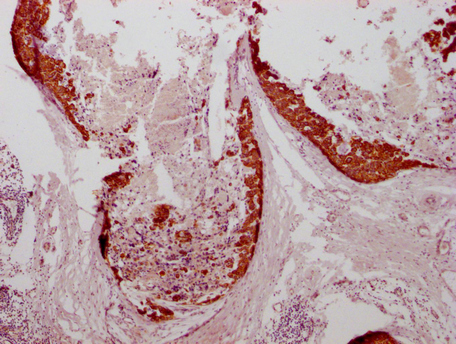

• IHC image of CSB-MA634481 diluted at 1:100 and staining in paraffin-embedded human breast cancer performed on a Leica BondTM system. After dewaxing and hydration, antigen retrieval was mediated by high pressure in a citrate buffer (pH 6.0). Section was blocked with 10% normal goat serum 30min at RT. Then primary antibody (1% BSA) was incubated at 4°C overnight. The primary is detected by a Goat anti-mouse IgG polymer labeled by HRP and visualized using 0.05% DAB.

IHC 1:20-1:200